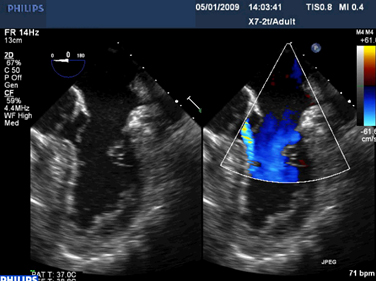

Mitral regurgitation

Mitral valve P2 leaflet prolapse: 2D view

From the collection of Prakash P. Punjabi